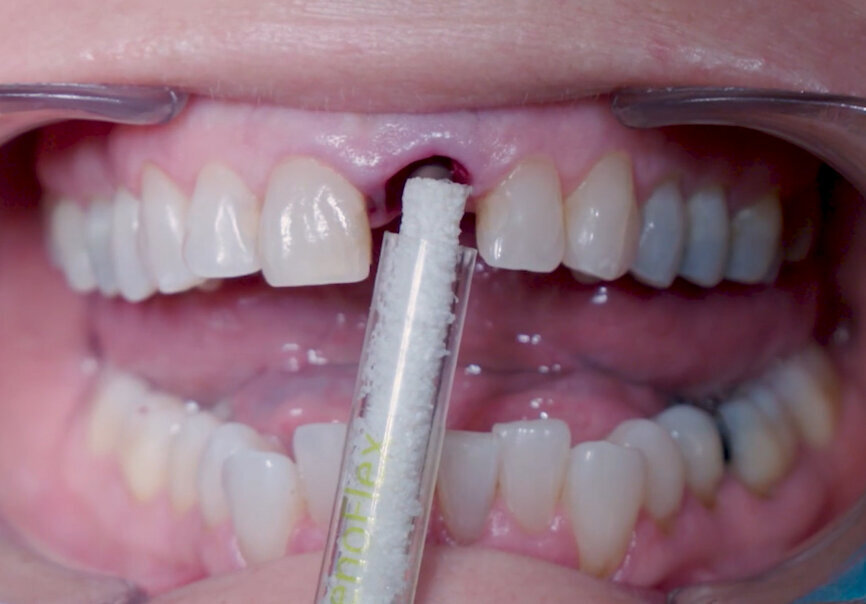

Fig. 14: Straumann XenoFlex being applied in labial gap.

Fig. 15: Straumann XenoFlex being applied in labial gap.

Intra-sulcular incisions were performed to release the marginal gingival fibres to allow a minimally invasive extraction. The socket was carefully cleaned to remove any ligament and debris left. Special attention was given to assessing the alveolar wall integrity. A distance of 3 mm was observed between the gingival margin and the labial wall margin. Implant bed preparation considered a medium-density bone workflow, starting with the needle drill aimed at the palatal wall to create an entry point for the next drills, creating an osteotomy that allows for a greater area of implant engagement (Fig. 5). The Ø 2.2 mm pilot drill was used to the respective implant length planned, followed by the use of an alignment pin to check the 3D orientation (Figs. 6 & 7). The Ø 2.8 mm and Ø 3.2 mm drills were used to finalise the osteotomy (Fig. 8). The site was then properly probed to assess for possible wall perforation. A 4 × 14 mm implant was placed, starting with the surgical handle engaging the apical part of the implant, following the same orientation as that of the needle drill and correcting the implant direction as it moved within the osteotomy (Figs. 9 & 10). Primary stability (45 Ncm) was achieved at the final position. After placement, the implant position was verified horizontally with an occlusal mirror and vertically with a surgical probe, and at this point, the abutment gingival height was selected (Figs. 11 & 12). A healing abutment was placed on to the implant (Fig. 13) to protect the connection so that granular bone substitute (Straumann XenoFlex) could be applied in the gap between the implant and labial wall. This was gently compacted in with the 2.8 mm side of the surgical probe (Figs. 14–16). Collacone (botiss biomaterials) was used to keep the bone granules away from the gingival margins in order to avoid softtissue fenestration and fibroblastic infiltration (Figs. 17 & 18).